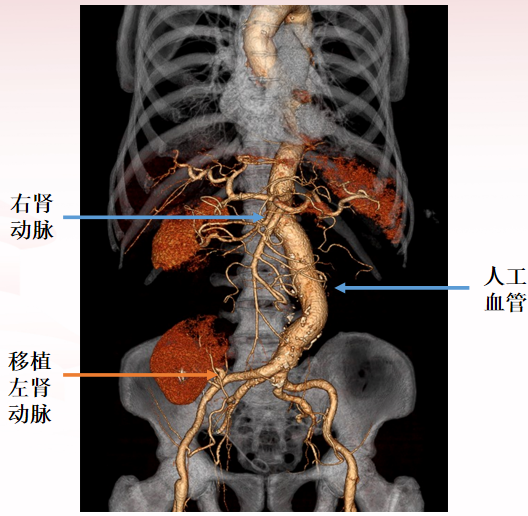

近肾腹主动脉瘤-1

男性,49岁

近肾腹主动脉瘤,左侧肾动脉受累,既往马凡综合征

手术方案:

腹主动脉瘤切除人工血管置换术 +左肾自体肾移植术

采用直筒型人工血管

术后6个月CTA

术后1年CTA

术后2年CTA